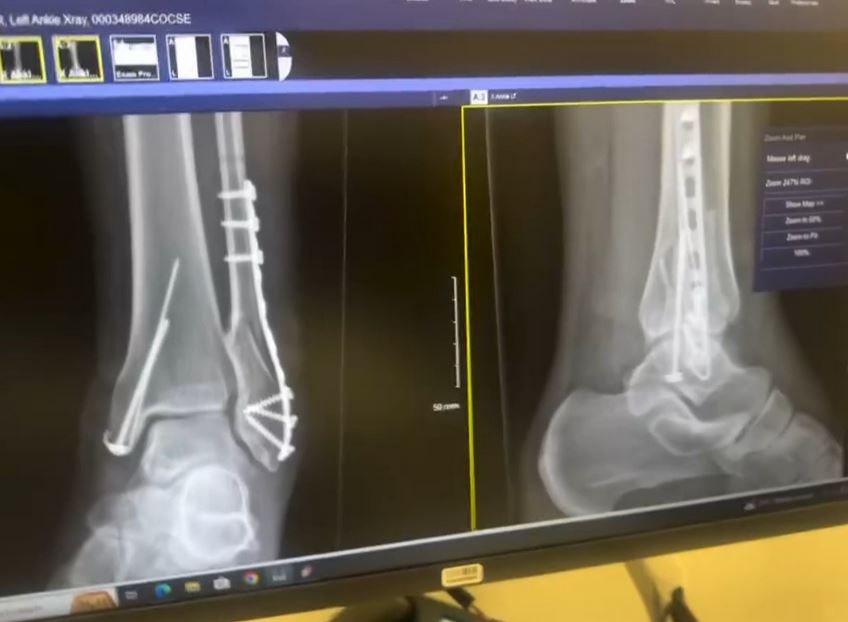

Popular Nigerian actress, Idia Aisien suffered an accident on July 6, and had to undergo surgery.

In an Instagram post, Idia revealed that she broke her leg in three places and was unable to walk.

She suffered a horrific accident that left her hospitalised for weeks and unable to walk.